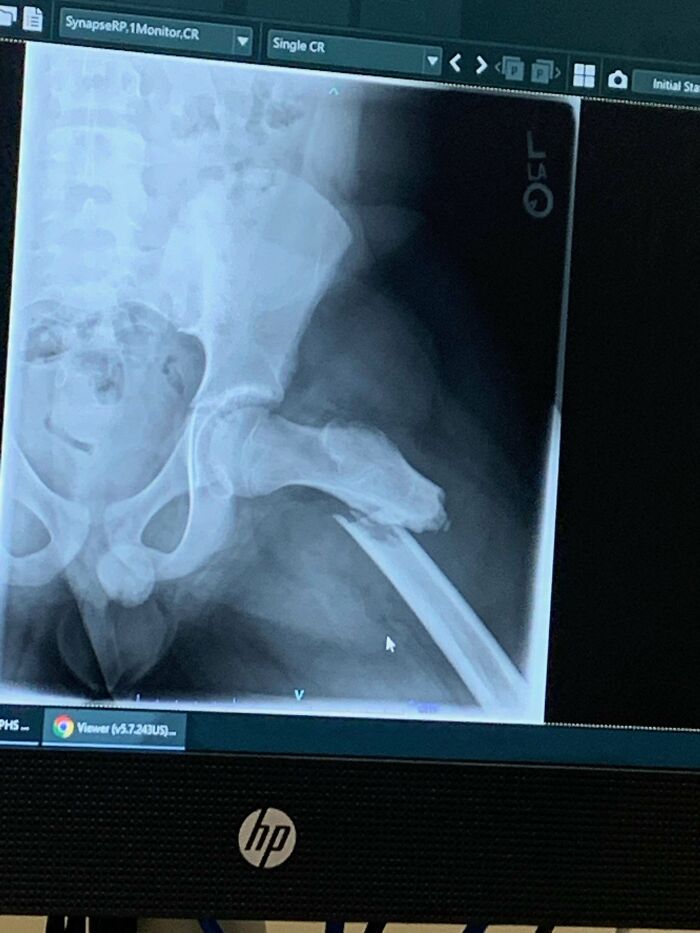

My Hip Died From Avn, Then I Woke Up In The Hospital Recovery Room Not Knowing The Replacement Was Dislocated

Some general info on my situation. Had developed on and off pain in my left leg/hip for years till it got so bad I couldn't put my full weight on it, which is when I got in for the first image showing an MRI slice of the dead hip. Eventually I was able to get the hip arthroplasty done. I awoke in recovery with my leg flat on the bed. I complained to the initial Nurse's & PT people that it felt weird & shorter than it should be. The Drs and surgeon said normally patients felt it was longer, but it felt shorter to me and those initial people after the surgery told me that what I felt was "normal"... I figured I just had a hip replacement & it'd be painful... ~1.5 months later they did a Xray & well, that's why I couldn't walk like I'd read I should have been able too. Anteriorly dislocated the whole time. I kept bringing it up about it feeling weird with the med related people I was seeing... I suppose I was a bit stoic & didn't give the right number of the pain that I felt. Just thought they knew better than me. I feel like I have a permanent muscle knot at this point.

All it took was an Xray to find the problem but they couldn't be bothered for 1.5 months?? (the doctors not the patient)